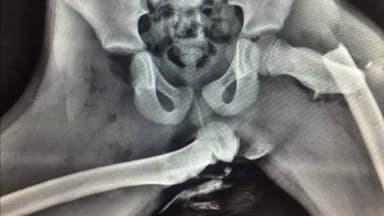

The image accompanying this article is an actual x-ray of such an injury caused by an airbag deploying in a crash whilst the passenger had their feet on the dashboard. Police in Wales released the image of the X-ray to show what they called the woman's "life changing" injuries.

Firstly, and this is for passengers (hopefully), please do not put your feet up on the dashboard (or out the car window)! We have already seen this happening this year. It is dangerous, and it is utterly stupid, which you will understand when you see the results of an impact injury caused by the inflation of an airbag, which can happen at a relatively slow speed. It is illegal, because it is so dangerous.

In the event of a crash, if a passenger is travelling with their feet up on the dashboard, the injuries that may occur will be very serious, partly as the deployment of the airbag can cause more serious injuries than it prevents in this situation, and, irrespective of an airbag being present, the glass from the windscreen can cause serious injury, not to mention the effects of a passenger being crushed by the impact between the dashboard and the seat.